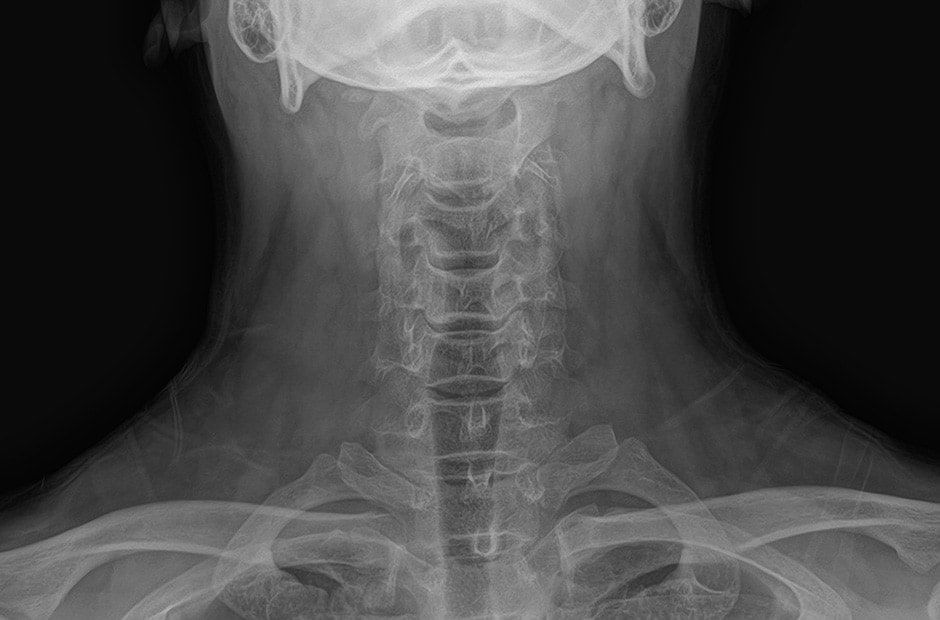

Klare Bilder erhalten